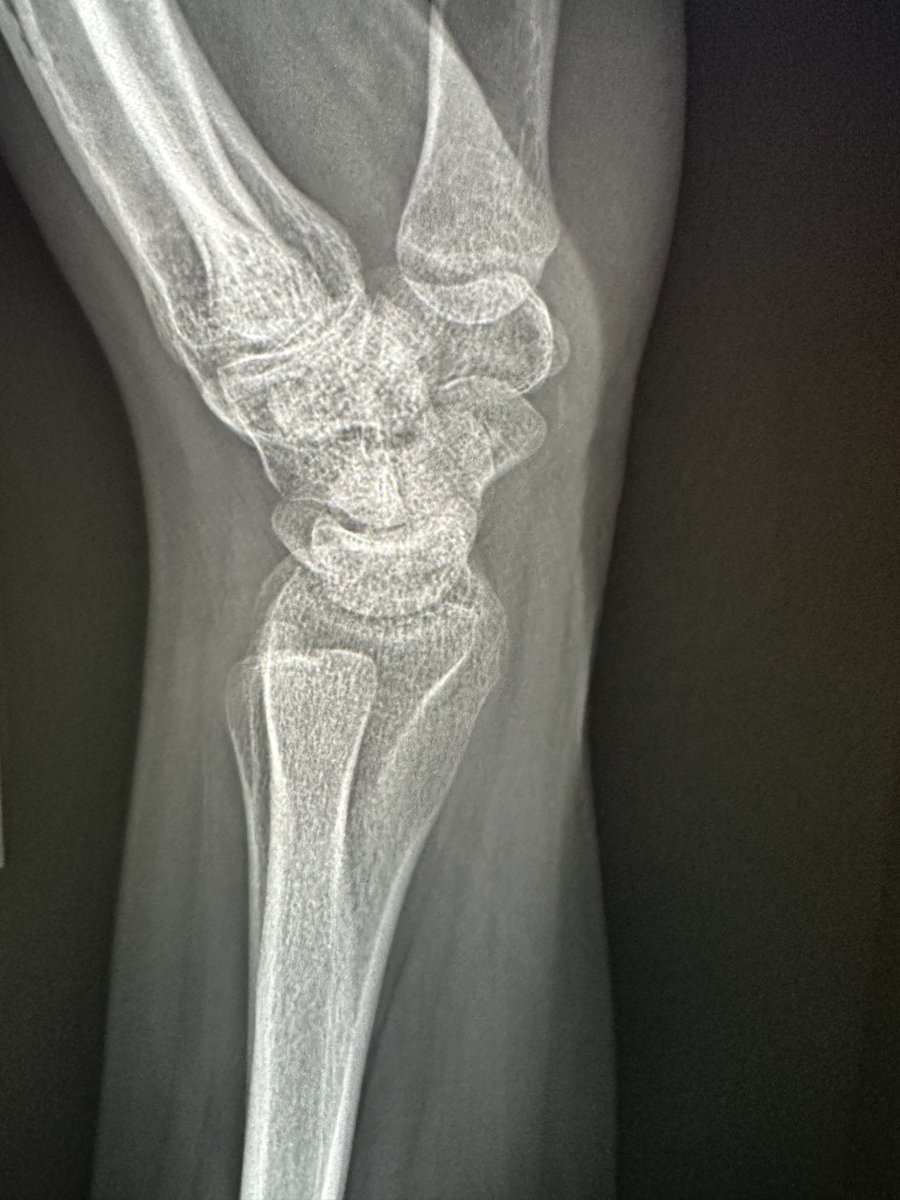

From twitter.com

RJ on Twitter "Young male. Flexion wrist injury. Persistent pain. Several nl radiographs. Call Wrist Injury Hyperflexion The inciting event typically involves the sudden application of a force, excessive load. Most sprains occur when the wrist is bent or twisted forcefully, such as in a fall onto. These exercises involve going through the different ways your wrist can move: Wrist sprains occur when a ligament is pathologically stretched, twisted, lacerated, or torn. Bend your wrist forward and. Wrist Injury Hyperflexion.